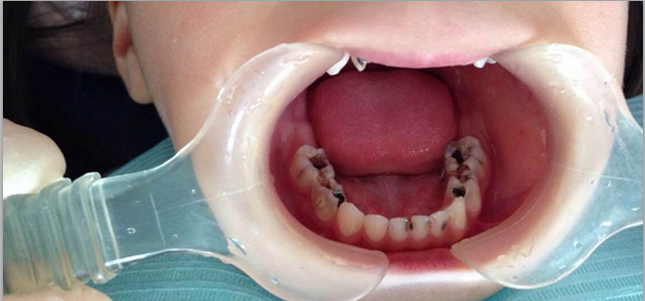

1、影响咀嚼功能:很多孩子两三岁,上门牙就坏没了,无法啃东西。有的孩子四五岁、五六岁,后牙大面积龋坏,导致咬合不佳,无法吃硬东西,连肉都咬不动。有的坏牙一吃东西就疼,孩子就表现为不爱吃东西。牙不好,胃口就不好,大人小孩都一样。>>点击在线咨询详情<<

2、影响美观:尤其是上前牙龋坏。现在很多家长不注意孩子的喂养习惯,上前牙龋坏高发。很多孩子三四岁,甚至一两岁,上前牙就黑了坏了没了。门牙的龋坏,不止影响美观,甚至可能对孩子的心理健康,产生负面影响。>>点击在线咨询详情<<

3、导致咬合异常:最常见的是牙列拥挤,因为乳牙邻面龋坏或者因龋早失导致间隙缩窄,恒牙没有足够萌出空间,因此长的里出外进,拥挤不堪。乳牙龋坏的危害有哪些?>>点击在线咨询详情<<

4、导致恒牙龋坏:龋齿是有一定传染性的疾病,乳牙龋坏多的孩子,往往刷牙不认真饮食习惯差口腔卫生差致龋菌含量高,导致恒牙患龋的风险大增,其中的重灾区就是“六龄齿”——即孩子6岁左右萌出的第一恒磨牙,因萌出时间早易被误认为乳牙而导致严重龋坏却得不到及时治疗。>>点击在线咨询详情<<